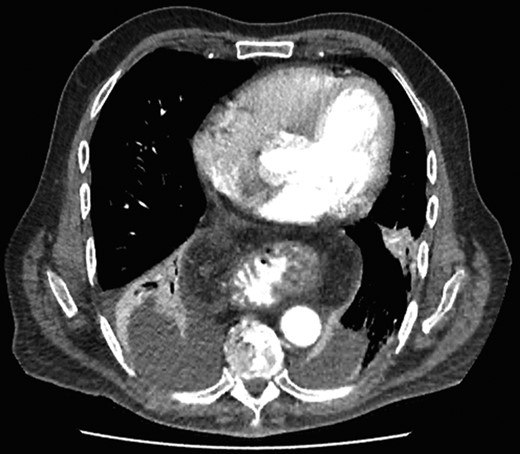

Nasojejunostomy tube was inserted and feeds were commenced. Interval gastroscopy in 2weeks revealed superficial sloughing of esophagus from 27 to 34 cm consistent with partial thickness esophageal necrosis (Fig. 7). Clear fluids were commenced and gradually upgraded to full diet over the course of 6 weeks. Follow-up gastroscopy at 9 weeks showed completely healed mucosa (Fig. 8).

Interval endoscopy at 2 weeks showing signs of healing (Superficial slough at the area of partial necrosis).